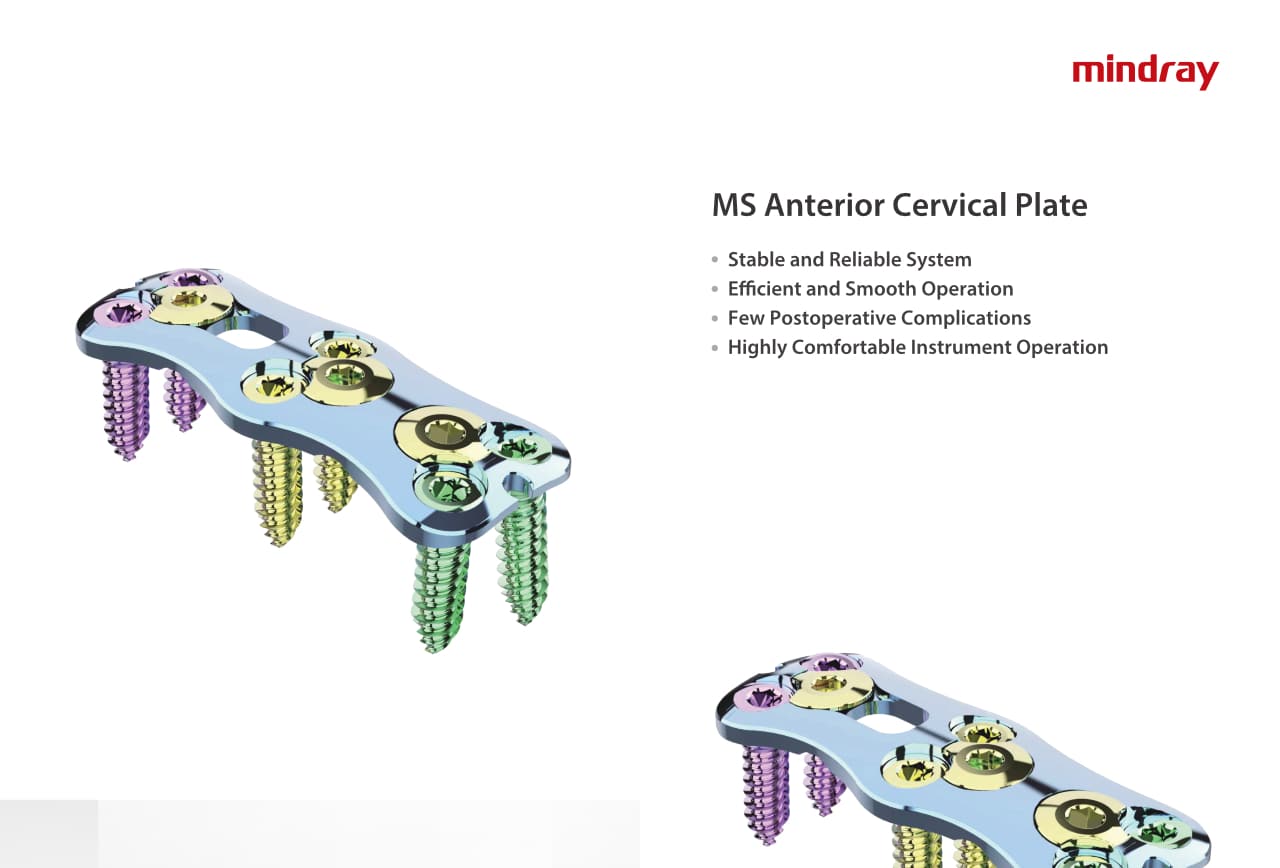

–Ю—А—В–Њ–њ–µ–і–Є—З–µ—Б–Ї–Њ–µ –њ–Њ–і—А–∞–Ј–і–µ–ї–µ–љ–Є–µ –Ї–Њ–Љ–њ–∞–љ–Є–Є Mindray, —А–∞—Б–њ–Њ–ї–Њ–ґ–µ–љ–љ–Њ–µ –≤ –£—Е–∞–љ–µ, —П–≤–ї—П–µ—В—Б—П –Њ–і–љ–Є–Љ –Є–Ј –≤–µ–і—Г—Й–Є—Е –њ—А–Њ–Є–Ј–≤–Њ–і–Є—В–µ–ї–µ–є –Њ—А—В–Њ–њ–µ–і–Є—З–µ—Б–Ї–Њ–є –њ—А–Њ–і—Г–Ї—Ж–Є–Є –Є–Ј –Ъ–Є—В–∞—П. –Ю–љ–Њ –Ј–∞–љ–Є–Љ–∞–µ—В—Б—П –Є—Б—Б–ї–µ–і–Њ–≤–∞–љ–Є—П–Љ–Є –Є —А–∞–Ј—А–∞–±–Њ—В–Ї–Њ–є, –њ—А–Њ–Є–Ј–≤–Њ–і—Б—В–≤–Њ–Љ –Є –Љ–∞—А–Ї–µ—В–Є–љ–≥–Њ–Љ —В—А–∞–≤–Љ–∞—В–Њ–ї–Њ–≥–Є—З–µ—Б–Ї–Є—Е –Є —Б–њ–Є–љ–∞–ї—М–љ—Л—Е –Є–Ј–і–µ–ї–Є–є, –њ—А–Њ–і—Г–Ї—Ж–Є–Є –і–ї—П –∞—А—В—А–Њ–њ–ї–∞—Б—В–Є–Ї–Є –Є –і—А—Г–≥–Є—Е —Е–Є—А—Г—А–≥–Є—З–µ—Б–Ї–Є—Е –Є–Ј–і–µ–ї–Є–є. –° –Љ–Њ–Љ–µ–љ—В–∞ —Б–≤–Њ–µ–≥–Њ –Њ—Б–љ–Њ–≤–∞–љ–Є—П –≤ 1999 –≥–Њ–і—Г –Љ—Л —Г—Б–њ–µ—И–љ–Њ –њ—А–Њ—И–ї–Є —Б–µ—А—В–Є—Д–Є–Ї–∞—Ж–Є—О ISO 9001, ISO 13485 –Є CE, –≤—Л–і–∞–љ–љ—Г—О T?V –Є —Н–Ї—Б–њ–Њ—А—В–Є—А—Г–µ–Љ –њ—А–Њ–і—Г–Ї—Ж–Є—О –≤ –±–Њ–ї–µ–µ —З–µ–Љ 50 —Б—В—А–∞–љ –њ–Њ –≤—Б–µ–Љ—Г –Љ–Є—А—Г.